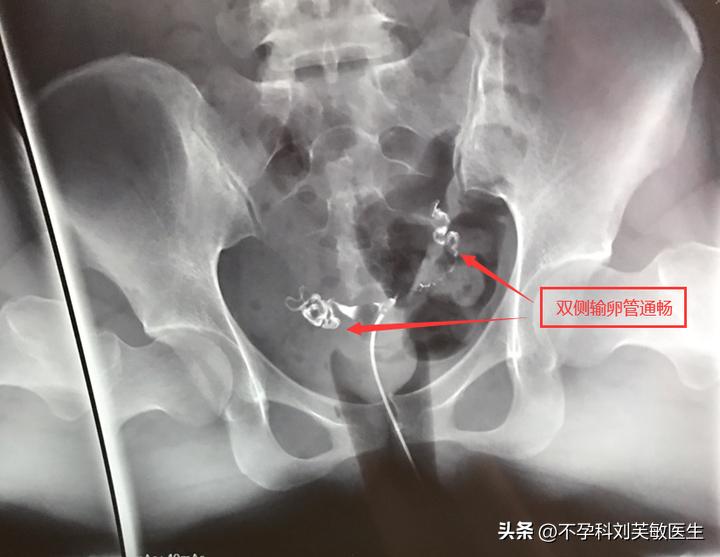

1.输卵管通畅

造影片可以看到一侧或双侧输卵管伞端有造影剂溢出,盆腔有造影剂均匀涂抹。 这种情况表明输卵管是通畅的,排除其他导致不孕的因素,查后积极试孕,不久就会有好消息的哦!